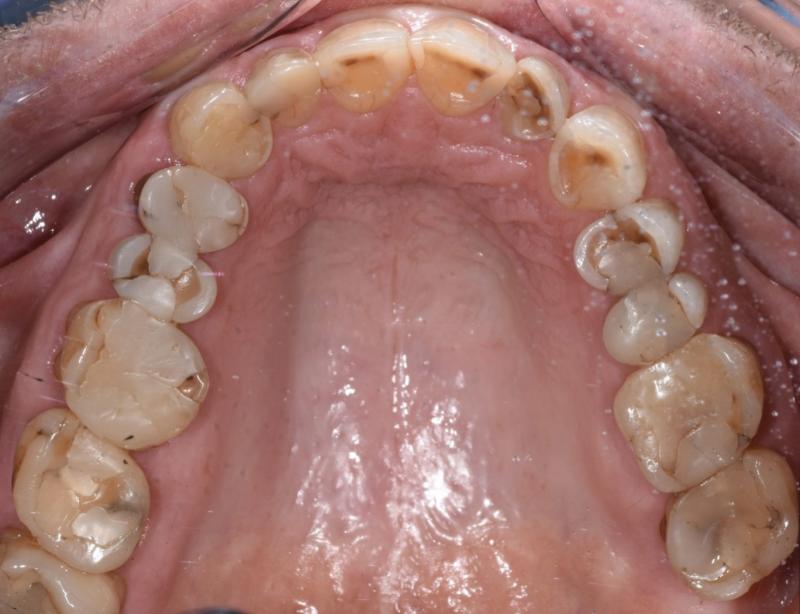

"En typisk mun efter 30 år med komposit. Patienten lider av food impaction och är trött på att få göra om fyllningar varje år." Bild: Johan Hagman